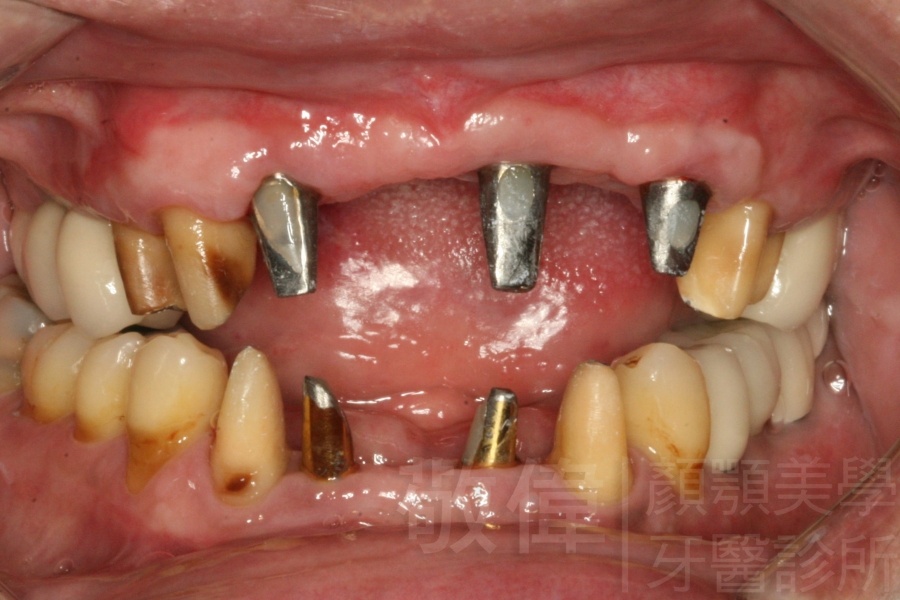

人工植牙/因嚴重牙周病而缺牙的植牙重建

嚴重牙周病   拔除牙周病牙齒

植牙的支台柱   裝上假牙完成